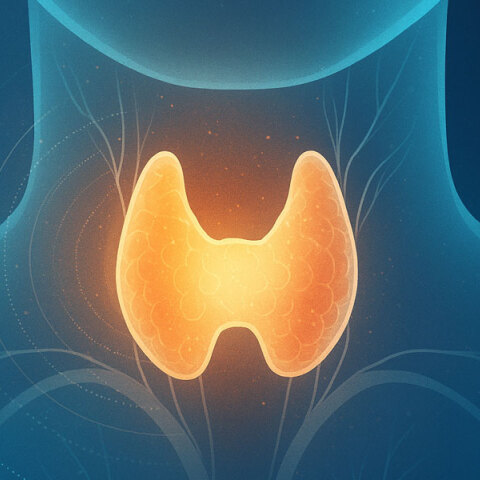

ΚΑΡΚΙΝΟΣ ΘΥΡΕΟΕΙΔΟΥΣ

Καρκινος Θυρεοειδους

Ο Γεώργιος Σακοράφας, χειρουργός θυρεοειδούς – παραθυρεοειδών, μας εξηγεί τα βήματα της διάγνωσης και της θεραπείας

Ο ρόλος του θυρεοειδούς στη διαχείριση του σωματικού βάρους

Η συνηθέστερη μορφή καρκίνου των ενδοκρινών αδένων

Η συχνότητά του έχει παρουσιάσει σημαντική αύξηση τις τελευταίες δεκαετίες

Ο Γεώργιος Σακοράφας, M.D., Ph.D., Χειρουργός Θυρεοειδούς και Παραθυρεοειδών, μας δίνει τις απαντήσεις

Απαραίτητες οι τακτικές ιατρικές εξετάσεις για τον εντοπισμό της κακοήθειας σε αρχικό στάδιο